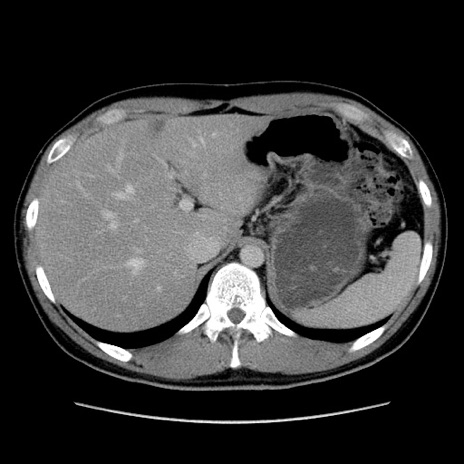

症例36(横断像)

【症例】20歳代 男性

【主訴】心窩部痛

【現病歴】今朝より上腹部痛あり。一旦軽快していたが再度出現したため救急要請。昨日夕に白身の魚を含む刺身を食べた。

【身体所見】BP 136/89mmHg、HR 74/min、BT 37.0℃、腹部:膨満、軟、心窩部に圧痛あり。反跳痛なし、筋性防御なし、腸雑音やや亢進あり。

【データ】WBC 17700、CRP 0.48